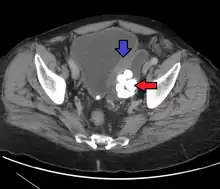

Diverticulum of the urinary bladder of a 59-year-old man, transverse plane

Bladder diverticula containing stones: the bladder wall is thickened due to possible transitional cell carcinoma.- Bladder diverticula as seen on ultrasound with doppler[18]